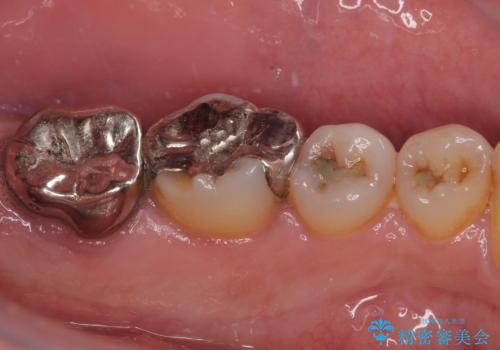

- 奥の銀歯が外れしまったとのことで来院された患者様です。

非常に咬合力が強く、銀歯の周りの歯がむし歯になっている状態でした。

ゴールドのような金属の詰め物は、削る範囲を最小限にし、厚みもセラミックと比べて薄くできるため、セラミックのようにクラウンにせずに治療を行うこともできますが、保険診療である銀歯では、どうしても適合が悪く隙間ができてしまうので、今回のような周辺がむし歯になる可能性が高くなってしまいます。